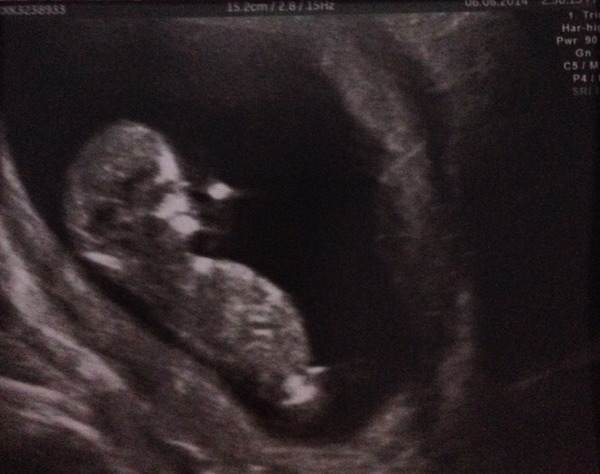

PolytheneGirl · 06/06/2014 22:40

I'm just showing off now! Grin Grin Grin

Lovely Poly how many weeks are you now?

poly can't believe how clear that picture is! Really lovely to see.

poly what a fab scan pic. Yey.

What a lovely scan picture poly!

Awww, Poly, gorgeous scan photo. :)

And totally fab scan pic poly so pleased for you and lovely to be able to tell everyone at last :)

Poly what a fab scan pic Smile

Oh I love a good scan picture, what great news Poly !